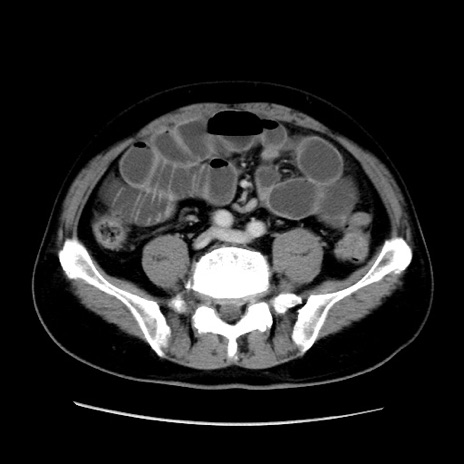

症例16(横断像)

【症例】 70歳代男性

【主訴】 腹痛、嘔吐

【現病歴】 約1ヶ月前より間欠的に腹痛と嘔吐あり、当院消化器内科を受診したところCTで多発する肝臓のLDAを指摘され、精査中であった。以降は消化器症状は安定していたが、2日前より嘔気と腹痛があり、同日より排便・排ガスが消失した。改善認めず、 本日、救急外来を受診した。

【身体所見】意識清明・会話良好、BT 36.3℃、BP 127/80mmHg、 P 80bpm、腹部:膨満あり、平坦・軟、上腹部正中および下腹部正中に圧痛あり、反跳痛なし、筋性防御なし。

【データ】WBC 7200、CRP 0.77